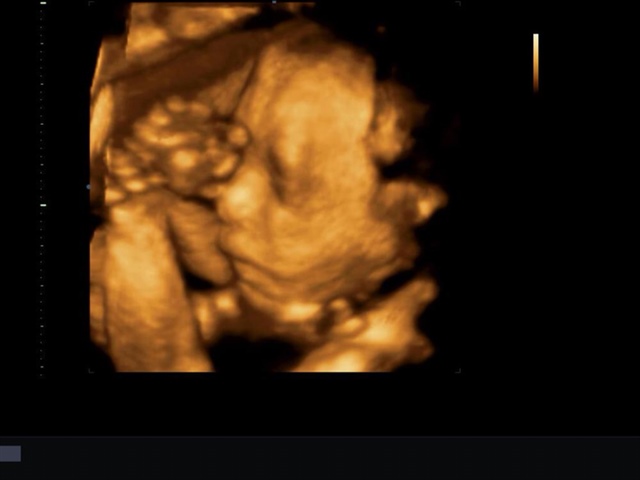

孕14周+6天

孕23周+4天

孕14周+3天

李李狐狸💋[帖主]:可惜是个男宝宝,压力倍增,两个儿子👦

李李狐狸💋[帖主]:做四维医生说的……